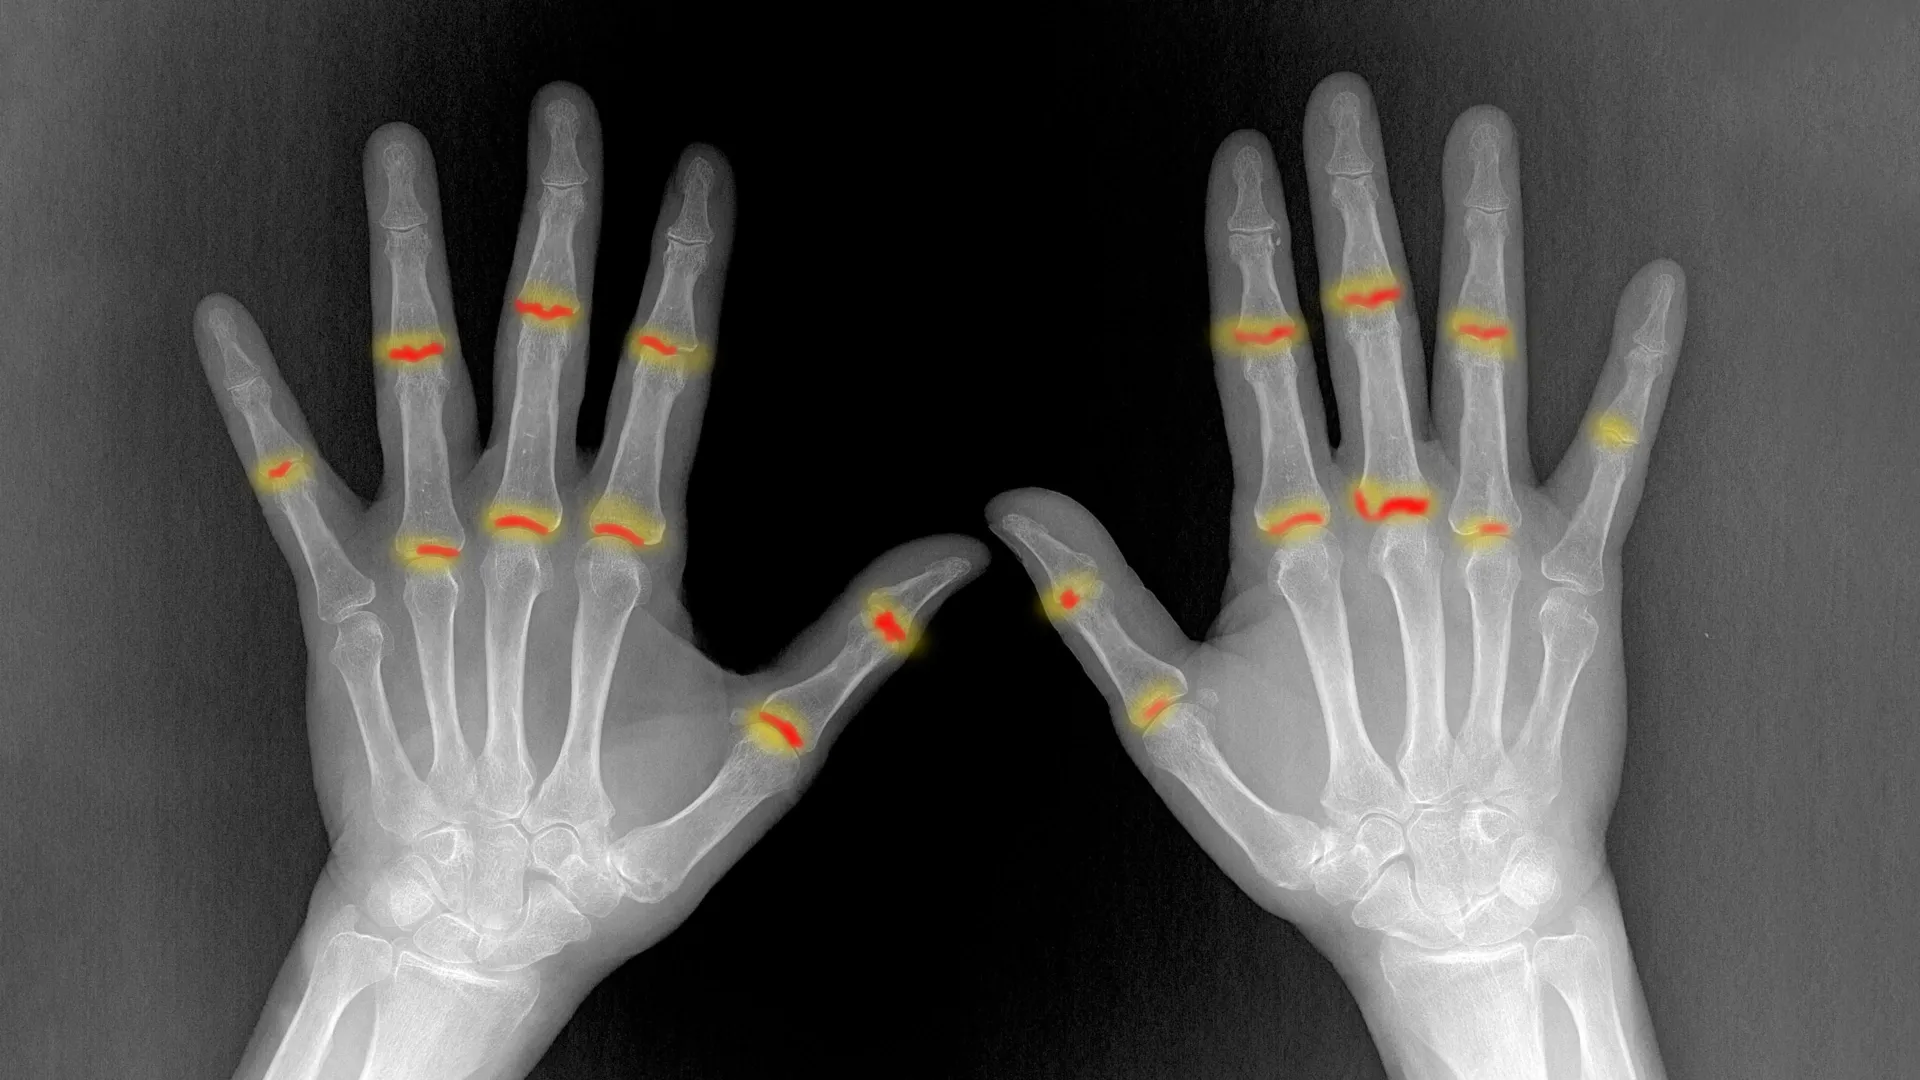

A significant proportion of individuals diagnosed with psoriasis, estimated between 20% and 30%, face the subsequent development of a debilitating inflammatory condition affecting their joints, known medically as psoriatic arthritis. This secondary ailment poses a serious threat, capable of inflicting irreversible damage to skeletal structures and articular tissues if left unaddressed. For an extended period, the precise mechanisms dictating why this progression occurs in a subset of psoriasis patients, while others remain unaffected, remained an enigma within the medical community.

The pivotal determinant, according to the study’s findings, lies within the microenvironment of the joint itself and the interaction of these incoming immune cells with resident joint tissues. Specifically, the research highlights the role of fibroblasts, which are fundamental connective tissue cells normally tasked with maintaining the structural integrity and protective equilibrium of the joint. In individuals who ultimately develop psoriatic arthritis, the study reveals a significant impairment in the functional capacity of these fibroblasts.

Professor Dr. Andreas Ramming, a team leader and deputy head of the department, elaborated on this finding, stating, "The intrinsic protective function of these connective tissue cells is typically considerably compromised in individuals who subsequently develop psoriatic arthritis." This diminished protective capacity creates an environment where the infiltrating inflammatory cells are no longer effectively regulated or suppressed. Consequently, the unchecked inflammatory cells proceed to elicit a robust inflammatory response within the joint, thereby initiating the characteristic pathology of psoriatic arthritis. This intricate interplay between the migrating immune cells and the compromised joint environment provides a compelling explanation for the differential susceptibility observed among psoriasis patients.